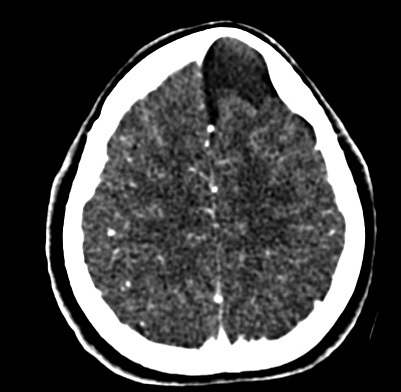

The CT scan also showed an underlying hypoattenuating, supratentorial lesion in the left frontal lobe and interhemispheric space, which was oval in shape with regular and well-defined borders, suggesting an arachnoid cyst that did not cause a shift in the midline structures when the left frontal lobe was compressed (Figure 2).